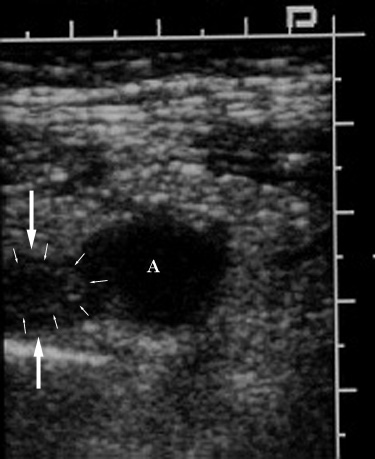

Figure 2. Ultrasound image obtained near Figure 1 in

an oblique plane shows an echovoid fluid collection (A)

representing a small abscess adjacent to a portion of the

abnormal appendix (large arrows). As noted above, there

is loss of the expected multilayered appearance of the

appendix; only a single echogenic layer representing the

submucosa (small arrows) is present in its tip. |